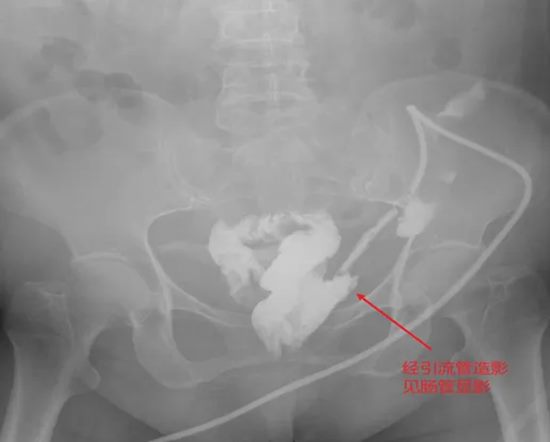

病例七:四次清创仍找不到瘘口?一场“侦探式”的寻瘘之旅

病情简述:患者胰十二指肠术后并发胆瘘、胰瘘、肠瘘,外院四次清创仍无法控制,瘘口位置不明。

诊疗破局:明确诊断是治疗的起点。团队通过精心设计的多次、多途径造影检查,最终精准定位瘘口位于结肠肝区。明确“敌情”后,先通过营养支持稳住“阵地”,再行回肠造口转流,为后续治疗创造了条件。

技术体现:在复杂的术后并发症中,“诊断先行”的思维是个体化序贯治疗的核心。